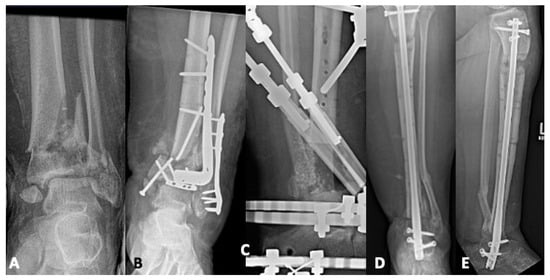

5.1. Revision Operative Fixation